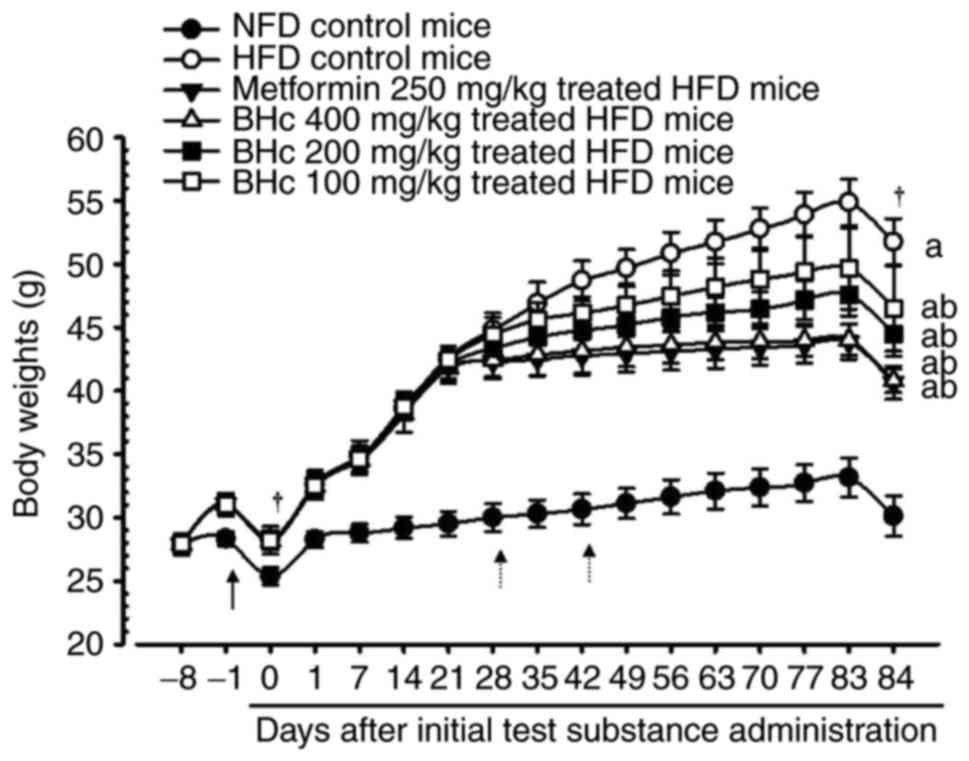

Significant increases in the body weight of HFD

administration. However, significant (P<0.05) decreases in the

body weights were observed in the metformin (250 mg/kg) and BHe

(200 and 400 mg/kg)-treated mice at 28 days after HFD

administration, and at 42 days after initial administration in the

100 mg/kg BHe-treated group compared with in the HFD control mice.

Accordingly, metformin-(250 mg/kg) and BHe-treated mice exhibited a

significant (P<0.05) decrease in body weight gain during the 84

days of test material administration compared with in the HFD

control mice. All dosages of BHe (400, 200 and 100 mg/kg) resulted

in clear dose-dependent decreases in body weight and body weight

gain during the experimental period of 84 days compared with HFD

control mice (Table II; Fig. 1). The body weight change during

the experimental period (84 days of HFD) in the control group was

increased by 393.44% compared with in the healthy control; however,

the changes were −47.02, −21.97, −31.28 and −46.12% in metformin

(250 mg/kg) and BHe (400, 200 and 100 mg/kg)-treated mice compared

with in the HFD control mice, respectively.